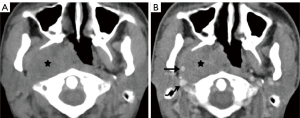

Lymphadenopathy is the most common pathology of the carotid space. A variety of primary diseases such as lymphoma, inflammation, and secondary diseases such as metastatic lymphadenopathy may involve lymph nodes, manifesting as masses of the carotid space. Enlarged lymph nodes, especially a solitary node, may mimic a primary tumor on CT and MRI. So, although the majority of lymphadenopathy is caused by metastatic tumors, we still describe them as “primary masses”. The imaging findings of diseased lymph nodes vary with different pathologies. Lymphoma may occur at any age with no gender difference, typically manifesting as painless or growing lymphadenopathy, and may have varying enhancement on CT/MRI imaging with extensive involvement and important neck structures encased yet without narrowing of arterial lumen (28-30). Metastatic lymphadenopathy is more frequently seen in middle-aged and elderly males and usually caused by head/neck squamous cell carcinoma, thyroid cancer, and so on. On CT/MRI imaging, it usually manifests as circular enhancement with central necrosis (squamous cell carcinoma), or obvious enhancement with cystic changes or calcification (thyroid cancer) (31-33). Lymph nodes in the carotid space lie anterior, lateral, and posterior to the jugular vein throughout its course in the neck (34). Therefore, enlarged lymph nodes in the carotid space will not be medial to any vessel in the carotid space (Figure 13), which is different from neurogenic tumors.